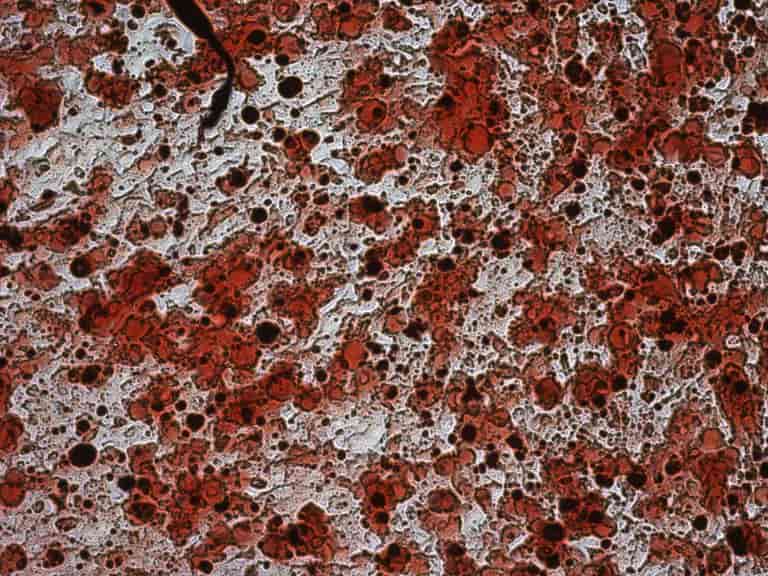

Das Lipödem ist nach der Definition der S1 Leitlinie AWMF eine chronisch progrediente Erkrankung, die nahezu ausschließlich bei Frauen auftritt und durch eine Fettverteilungsstörung mit deutlicher Disproportion zwischen Stamm und Extremitäten gekennzeichnet ist.

Diese entstehen aufgrund einer umschriebenen, symmetrisch lokalisierten Unterhautfettgewebsvermehrung. Zusätzlich bestehen Ödeme, die durch Orthostase verstärkt werden, sowie eine Hämatomneigung nach Bagatelltraumen. Charakteristisch ist eine gesteigerte Druckschmerzhaftigkeit, meist bestehen Spontanschmerzen. Die Ursache des Lipödems ist bisher unbekannt. Eine genetische Komponente wird aufgrund von positiven Familienanamnesen angenommen. Die erkrankten Fettzellen lassen sich nicht durch Sport oder Ernährungsmaßnahmen beeinflussen. Eine fehlende Transportfähigkeit der Lymphgefäße führt sekundär zu einem Stau an lipid-und proteinreichen Substanzen rund um die Adipozyten. Da der Abtransport nicht gewährleistet ist, kommt es zu einer vermehrten Ansammlung ebenfalls in den Adipozyten. Sekundär entwickeln sich in höheren Stadien ein chronisches Lymphödem und eine Fibrosierung der Adipozyten. Die charakteristische Fettverteilungsstörung der erkrankten Adipozyten lassen sich an den Extremitäten erkennen durch das Aussparen von Händen und Füßen, sowie einem typischen „Säulenbein“ und verstrichenen Konturen. Kennzeichnend für ein Lipödem ist außerdem die Gefäßfragilität, die sich durch ein leichtes Auftreten von Hämatomen bei inadäquatem Druck oder Berührung der Extremitäten ergeben. Des Weiteren klagen die Patientinnen meist über Ruheschmerzen in den Beinen, vor allem nach längerer Belastung. Die konservative Therapie mittels Kompressionstherapie und manueller Lymphdrainage beschränkt sich auf die symptomatische Linderung.

Die einzige nachgewiesene Therapie des Lipödems ist die radikale zirkuläre Liposuktion, die mit überdurchschnittlich hohen Kosten einhergeht und von den Krankenkassen in der Regel nicht übernommen wird. Diese Form der Therapie zeigte in Langzeitstudien eine Wiederherstellung einer hohen Lebensqualität und kaum Rückfallquoten. Aktuell gibt es eine unklare Studienlage zur Pathogenese des Lipödems und kaum Forschung zur molekularen Ätiopathogenese. Ziel dieser Studie ist es daher, die molekularbiologische Pathogenese dieses Krankheitsbildes zu erforschen und die Adipozyten in vitro Kultur auf unterschiedliche Faktoren zu untersuchen. Alle für die Studie ausgewählten Patientinnen leiden an Lipödem vom Ganzbeintyp (nach Herpertz) im Stadium II Grad II (nach Fife, Meier-Vollrath). Die Vergleichsgruppe wird von Patientinnen ohne diagnostiziertes Lipödem gebildet, deren Fettzellen durch die gleiche Liposuktionsmethode gewonnen werden.

Die Studie wird in Kooperation mit der Praxis Dr. Dominik von Lukowicz durchgeführt, der sich als Facharzt für Plastischen und Ästhetische Chirurgie auf die Behandlung des Lipödems spezialisiert hat und über jahrelange Erfahrung im Bereich der speziellen Liposuktion bei Lipödem verfügt.

normales Fettgewebe I Lipödem-Fettgewebe